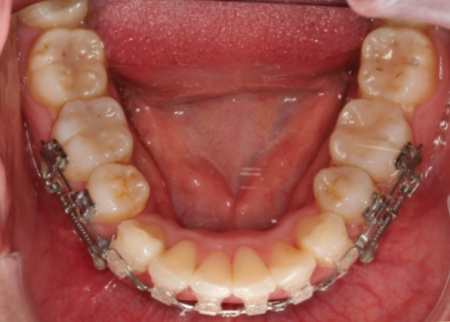

診断内容をお伝えした上で、歯を適切な位置に移動させるスペースを確保するために、上下左右の歯(第1小臼歯)の抜歯を行い、その後ワイヤー矯正と矯正治療用のバネ「クローズドコイル」を併用する「スピード矯正」を提案し、同意いただきました。

ワイヤー矯正では、歯の表面に接着した四角い装置(ブラケット)にワイヤーを通して歯を動かすマルチブラケット装置を使用します。

治療中の審美性を考慮して、前歯のブラケットは透明で目立ちにくいものを選択しました。

クローズドコイルは違和感や痛みがやや出やすいものの、バネの収縮力を利用して歯に対して一方向へ継続的に力をかけられるため、一般的な矯正治療と比べて治療期間の短縮や通院回数の減少が期待できます。

最初に上下左右の第1小臼歯を抜き、マルチブラケット装置とクローズドコイルを取り付け、歯並びを整えるレベリングを開始しました。

レベリングでは、ワイヤーの調整や交換を行いながら歯の傾きや回転を修正して向きを整え、それぞれの歯を適切な位置へ移動させます。

この段階でクローズドコイルを併用することで、より効率的に歯を動かすことができます。